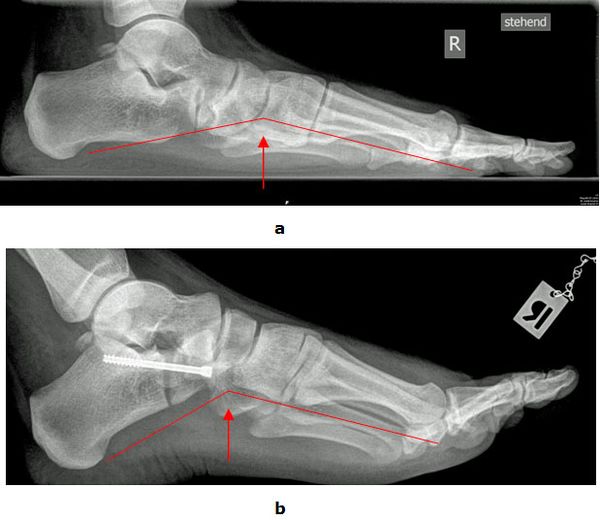

Achsanalyse durch Röntgen Belastungsaufnahmen

In der Röntgendiagnostik werden Belastungsaufnahmen des Fußes zur Bestimmung der Achsverhältnisse durchgeführt. Entscheidend ist das Verhältnis zwischen dem ersten Mittelfußknochen und dem Sprungbein sowie der Öffnungswinkel zwischen Fersenbein und Sprungbein. Die Winkel sind beim Plattfuß vergrößert. Außerdem wird der Gelenkzustand beurteilt.

Abb.3: a Absenkung des Längsgewölbes im Röntgenbild. Krankhafte Veränderung der Knochenachsen.

b Durch eine gelenkerhaltende Operationsmethode (Verlängerung des Fersenbeins (Evans Osteotomie, Calcaneus Verlängerungs Osteotomie) konnte der Fuß wieder aufgerichtet werden.